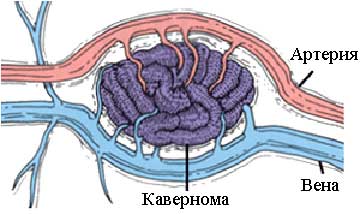

Врачи выделяют три основных типа ангиом: капиллярные, кавернозные и венозные. Каждый из этих видов имеет свои особенности и потенциальные риски. Капиллярная ангиома затрагивает сеть мелких капилляров, тогда как кавернозная форма представляет собой пещеристое образование багрового цвета с нарушенным кровотоком внутри.

Специфические каверномы наполняются кровью и иногда достигают значительных размеров. Осложнения возникают из-за хрупкости стенок сосудов, что может привести к мозговому кровоизлиянию.

Кавернозная ангиома

Каверны, представляющие собой сосудистые полости, являются основой этой серьезной патологии. Кавернозная ангиома головного мозга — это крайне опасное заболевание. Стенки каверномы разделены тонкими и не очень прочными перегородками. В случае разрыва образования может произойти мозговое кровоизлияние, что в свою очередь может привести к летальному исходу.

Медики называют кавернозную ангиому бомбой с замедленным действием. Кровоизлияние может произойти в любой момент, и предсказать этот критический момент крайне сложно. Запущенная форма заболевания может привести к серьезным нарушениям сознания, а также к параличу значительных участков тела.

Что такое кавернозная ангиома головного мозга?

Кавернозные ангиомы головного мозга (каверномы головного мозга) – врожденные патологические сосудистые полости в веществе мозга, внутри разделенные трабекулами и заполненные кровью, относящиеся к классу гемангиом.